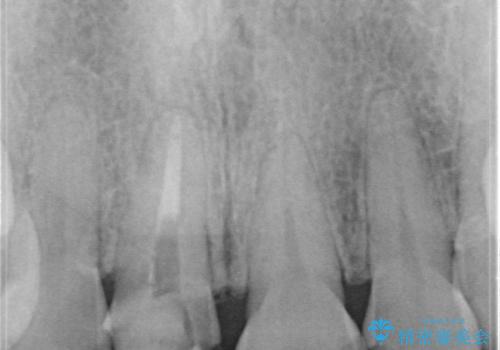

- 「他院で治療した前歯の被せものが一か月の間に2回外れたのでやり変えたい」を主訴に来院されました。

10年前に根管治療を他院で行っており、根尖性歯周炎の予防のため根管治療から行いました。被せものはオールセラミッククラウンで治療を行いました。

10年前にラバーダムシート無しに根管治療を行っており、現在、症状は出ていませんが、根尖性歯周炎の予防のため根管治療から行いました。ホームホワイトニングを2週間行って頂き、その後、オールセラミッククラウンで治療を行っています。

※根尖性歯周炎は根管内の細菌が原因となり発症します。唾液の中には数千億個もの細菌が存在します。したがって、ラバーダムシートを使用し、歯を唾液から守ってあげることが大切になります。当院では、ラバーダムシートの使用に加え、マイクロスコープ(歯科用顕微鏡)、P-MAX(超音波洗浄の機械)を使用して治療を行っています。